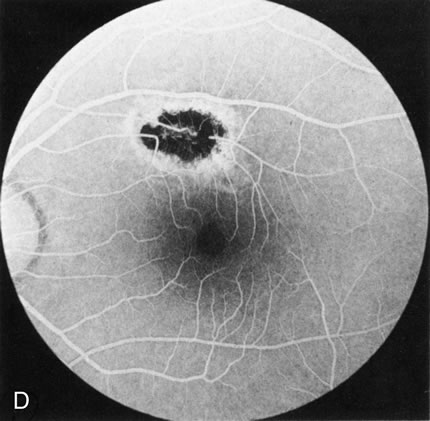

In retinitis pigmentosa (RP), the pigment abnormalities of atrophy, migration, and clumping are made apparent by transmitted hyperfluorescence and blocked hypofluorescence (Fig. 1A). Patients who have very minimal pigmentary alterations (pauci pigmentary RP) or no pigment abnormalities (RP sine pigmento) may show the abnormalities on fluorescien angiography (FA). It is uncommon to see choriocapillaris atrophy except in the late stages. This finding corresponds to the histopathology, which shows that the earliest abnormalities are in the photoreceptors and that the choroid is normal.1

Fig. 1. Retinitis pigmentosa. A. A typical area of bone spicule pigmentation. B. Diffuse dye leakage is apparent throughout the posterior pole. C. The early angiogram shows dilated and irregular retinal radial peripapillary capillaries and perifoveal retinal capillaries. D. Leakage from these vessels are evident in the late angiogram.

Dye leakage in RP may occur from the retinal vessels or at the level of the retinal pigment epithelium (Fig. 1B).2–4 The leakage may be seen in the macula and posterior pole, along the vascular arcades in the distribution of the radial peripapillary capillaries, and in the periphery (where an exudative vasculopathy resembling Coats' disease is suggested).

Of more clinical importance is the role of FA in the diagnosis and treatment of cystoid macular edema (CME) (Fig. 1C and D). Stereoscopic FA indicates that the leakage, which may be diffuse or have the typical petaloid stellate appearance of CME, can come from the perifoveal retinal capillaries, from the choroid through the RPE, or from a combination of both sources.4 With the recent suggestion that CME in RP may be successfully treated with acetazolamide,5, 6 FA is thus important to document the diagnosis of CME, establish the origin(s) of leakage, and follow patients during and after therapy.